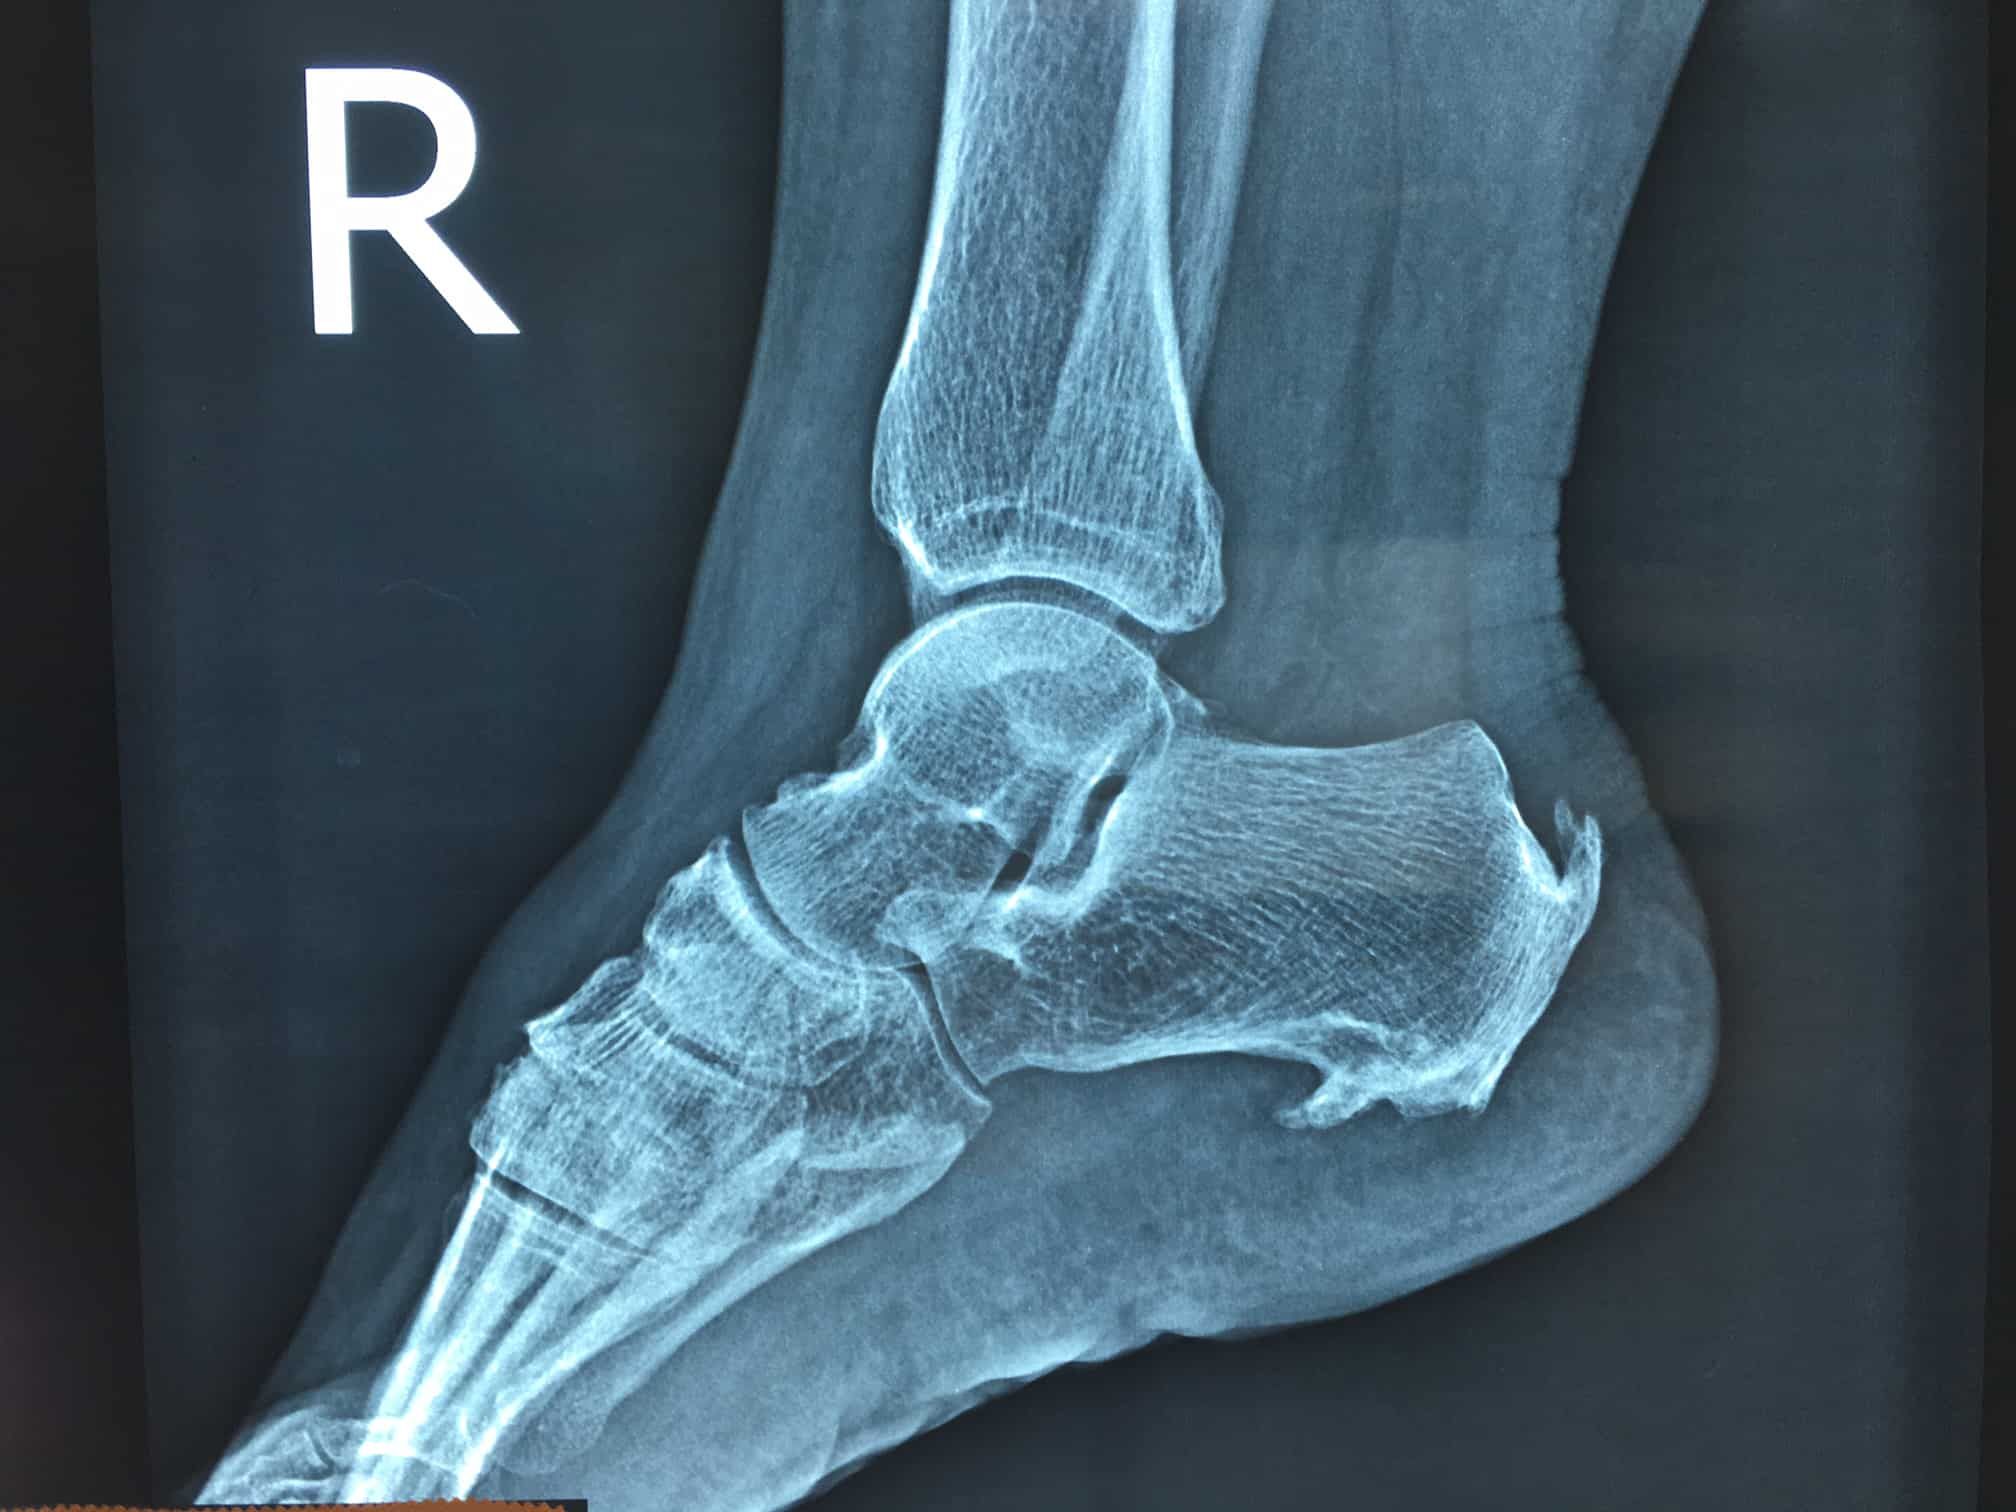

She visited her GP who spoke to her about a heel spur, he took x-rays and indeed there was a heel spur in the picture. He explained to her that generally very few surgeons will operate on heel spurs and there is little she can do but wait out the pain which on average would go away after about 18 months! He did give her some general stretches and said he could try an injection if she really wanted, but it was painful!